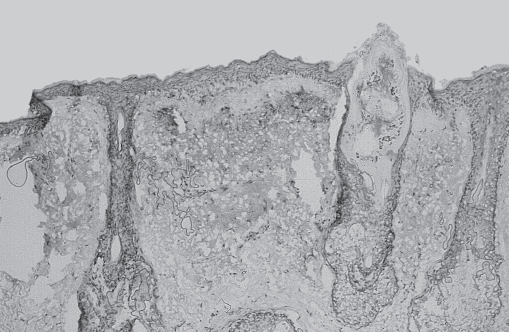

Histologic studies of biopsies taken immediately after laser resurfacing demonstrate a zone of tissue vaporization and ablation beneath which lies a basophilic zone of thermal necrosis ( Fig. 20.1 ).